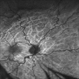

- Ultrawide field fundus photograph of a 62-year-old male with hypotony following blunt ocular trauma